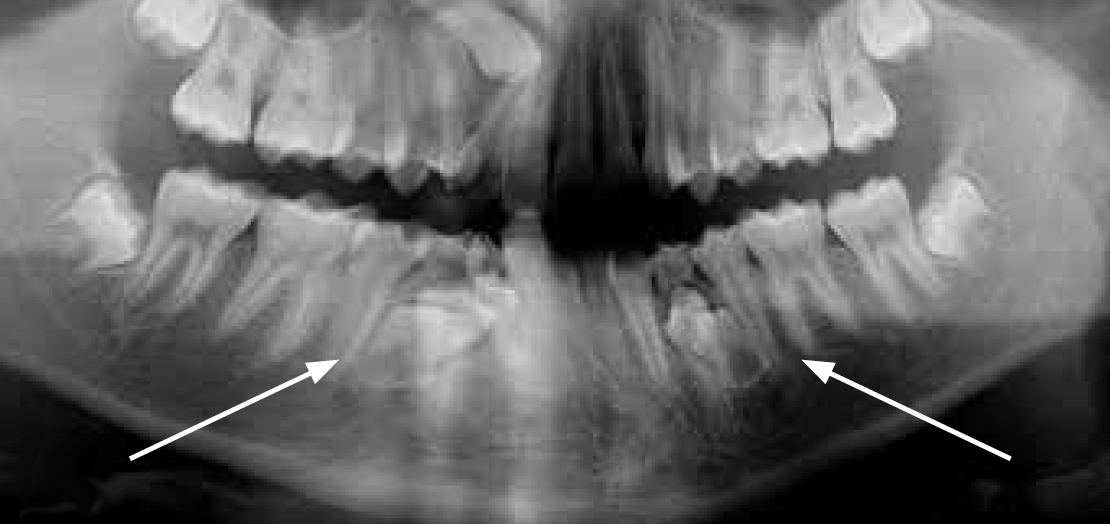

Fig 1. Functional shift in centric occlusion.

Figure 1

Fig 2. Functional shift in centric relation.

Figure 2

A common developmental abnormality is a localized anterior crossbite on permanent incisors, which may lead to trauma to these teeth. The most common cause of localized incisor crossbite is an anterior occlusal interference, which causes a functional shift when the patient moves from centric relation to centric occlusion (Figure 1 and Figure 2). This is not a true class III malocclusion, and proper diagnosis is critical to select the correct treatment. Sometimes this bite relationship is called a pseudo-class III relationship.2 Intervention in these cases is important because these teeth are at higher risk for recession, periodontal damage, and incisal chipping. Limited anterior braces and sometimes a palatal expander may be used to place the maxillary incisors facial to the mandibular incisors; this is referred to as "jumping the bite."